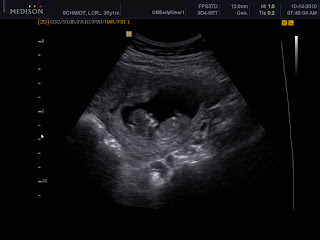

So our computer was broken for a while and now it is fixed!!!! I have been waiting to upload lots of cute pics, so I just decided to condense the whole month. We stared out the month by going to the pumpkin patch. She loved it especially the bounce house part. She LOVES animals so the feeding/petting zoo part was fun too. I had an ultrasound a few weeks ago and Wes decided to take the day off and we went to the zoo. We just love the Santa Barbara Zoo and she hadn't been there yet. She loved it and asks to go back all the time. When you ask her what her favorite animal was she says "the ducks." Silly girl. She really loved the monkeys and the lions. It was a beautiful day out, I don't think we could have gone on a more perfect day. We then had a little pumpkin painting party at out girls small group. Most of the kids dressed up and they all looked so cute. I just love having these girls in my life. Soon there will be 5 adults and 10 kids, almost all girls, so far just one boy on the way! The kids picked out pumpkins and then finger painted them. They all loved it. Next, Avery and daddy carved pumpkins. She loved it. This year she really understood the concept and really wanted to get in and help. Finally, on Halloween our neighbors had a party and we were invited for dinner and Trick or Treating afterward. I was so impressed with how she did. She walked around collecting candy for almost an hour! She kept up with the kids pretty well. She said "trick or treat" most of the time and always said "thank you and bye-bye." Lets just say she won a lot of peoples hearts, especially her mommy's. What a fun month it was.